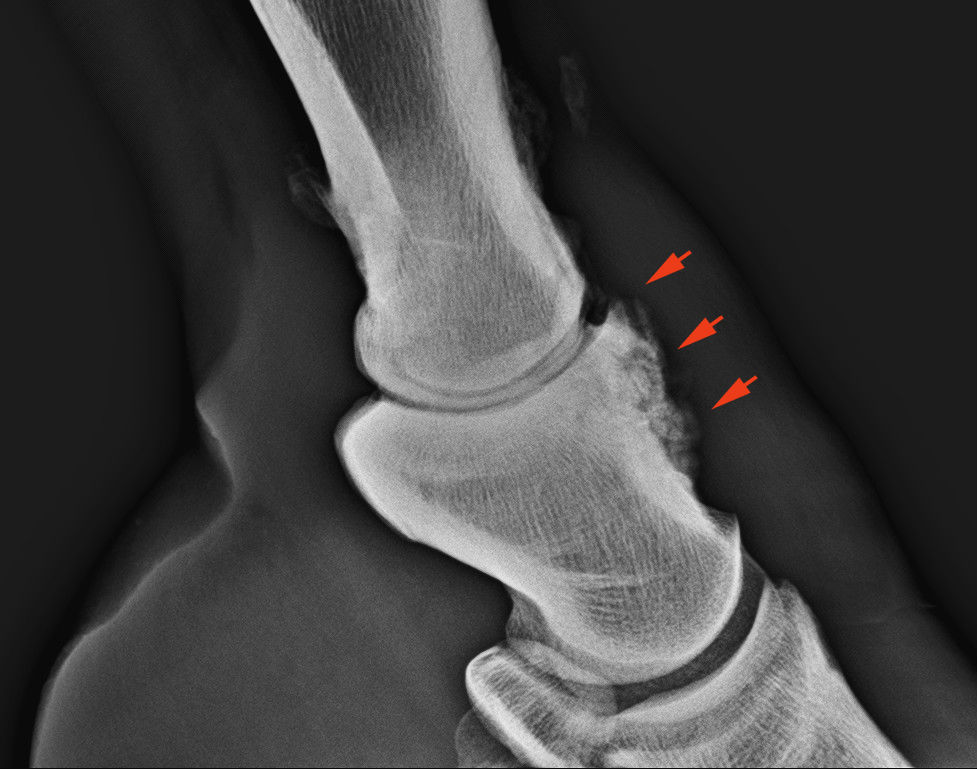

Csontfelrakódás (exostosis) a pártaízület krónikus gyulladásánál

A csontállomány növekedése esetén olyan csontfelrakódásokat láthatunk, melyek leggyakrabban a csont felszínén (például csonthártya gyulladás esetén), inak, szalagok, ízületi tok tapadásnál (enthezeophyta), az ízületi porc mellett (periarticularis osteophyta) vagy a csont állományában kialakuló meszesedés formájában (sclerosis) lehetnek. Csonthártya és ízületi betegségeket diagnosztizálunk ezeken az elváltozásokon keresztül.